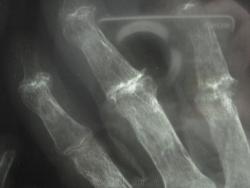

женщина,1930 г.р. , в наравлении -деформирующий артроз? В анализах повышено СОЭ, СРБ, ревмат. фактор.

Рентгенологически выделяют 4 стадии ревматоидного артрита: I стадия (начальная) — только околосуставной остеопороз; II стадия — остеопороз + сужение суставной щели; III стадия — остеопороз + сужение суставной щели + эрозии костей; IV стадия—сочетание признаков III стадии и анкилоза сустава. Раньше всего рентгенологические изменения при ревматоидном артрите появляются в суставах кистей и плюс-нефаланговых суставах.

Ревматологи с областной больницы ставят DS: Ревматоидный  артрит, акт. II. R-стадия III. НФС III. Вторичный ДОА III ст. Анемия хронических заболеваний.

Без псориаза и его кожных проявлений - псориатическую артропатию диагностировать трудно...